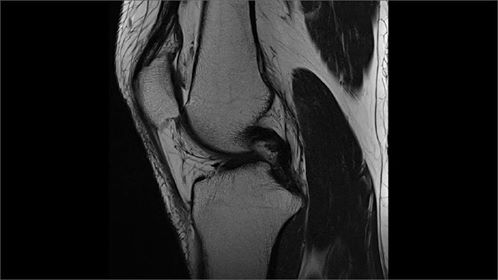

Izvid/diagnoza v petek: Dvakrat počen meniskus in Bakerjeva cista. Ampak ne skrbi so bile besede organizatorja. To vsak zmore.

Da je koleno fuč se jasno vidi tudi na sliki.